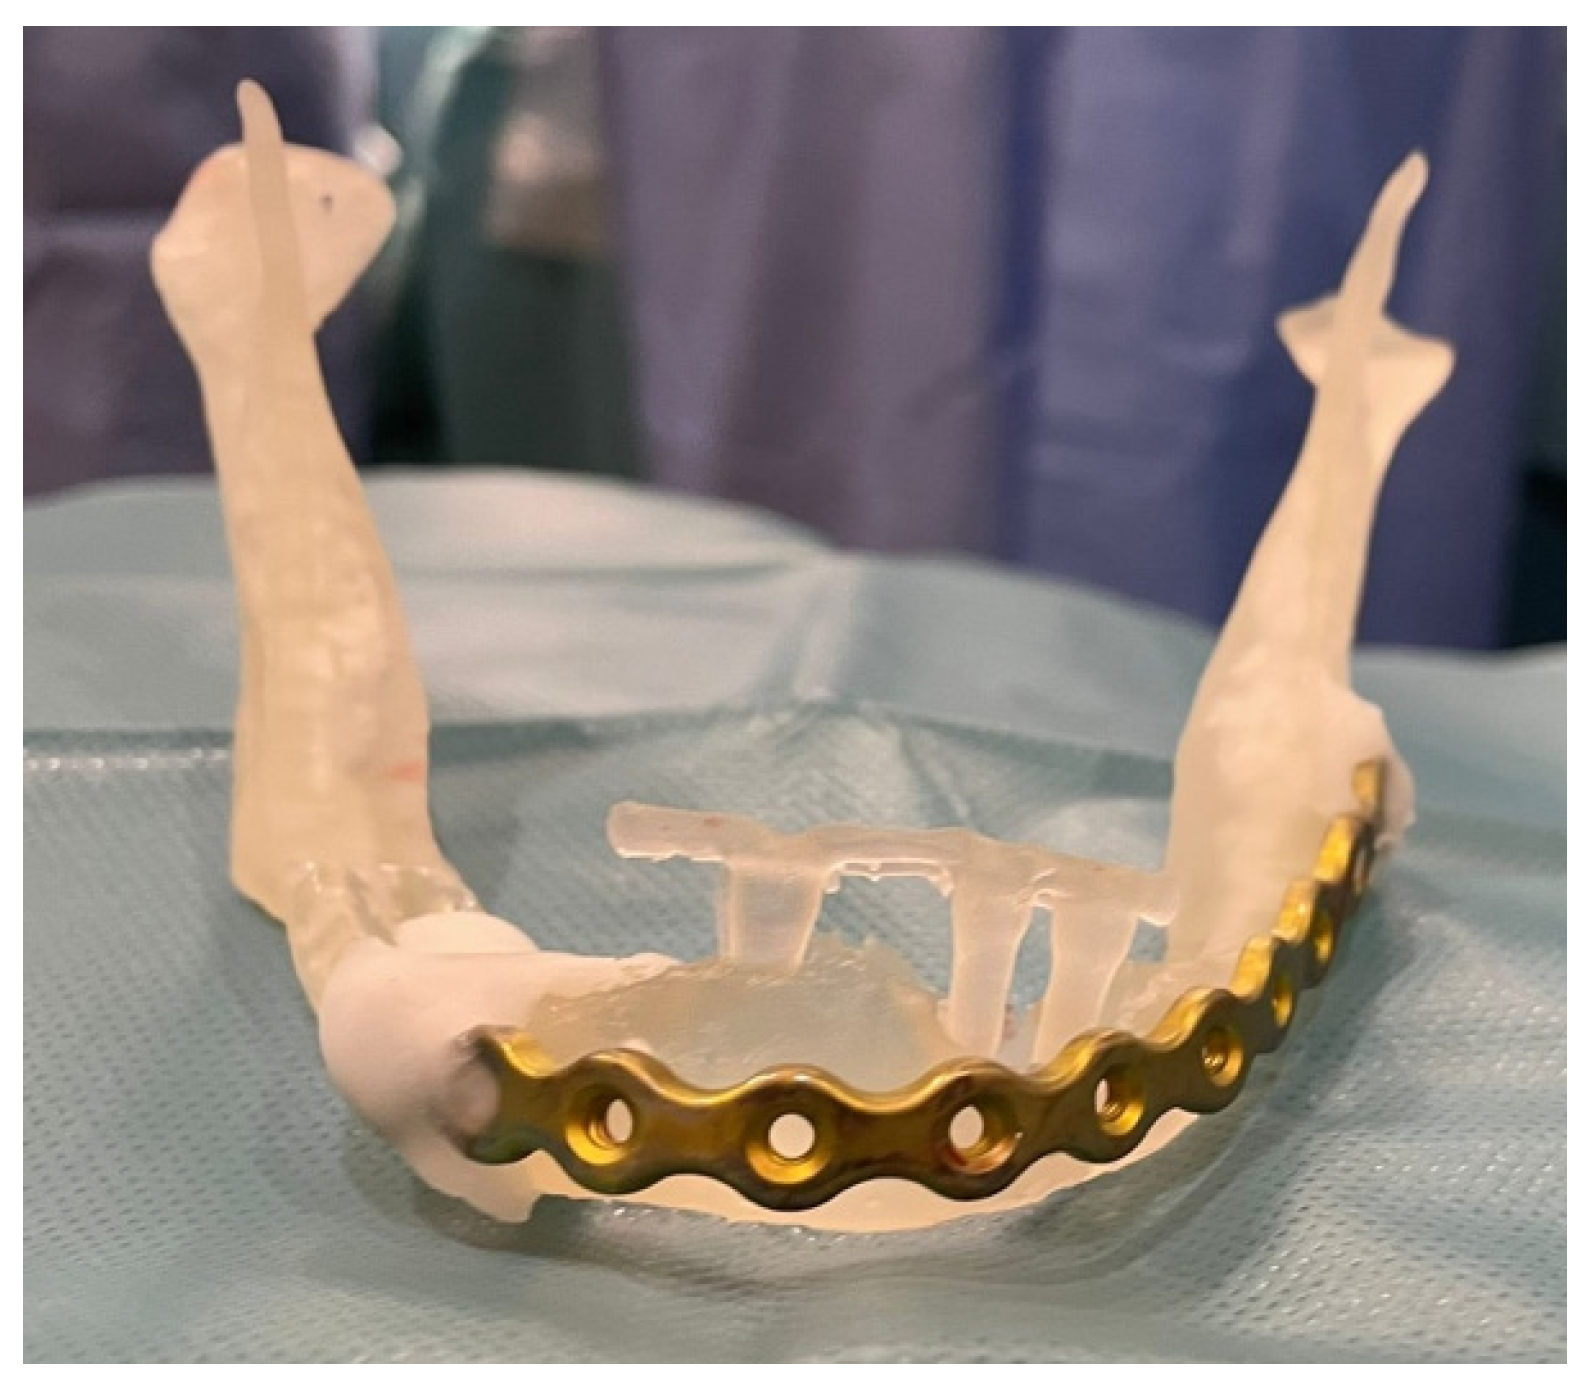

3.1. Case 1

3.2. Case 2

| Type of internal fixation | 2.5 mm thick mandibular locking plate with 2.4 mm screw diameter | 3 (50%) |

| 2.0 mm thick mandibular locking plate with 2 mm screw diameter + 1.0 mm thick mandibular plate with 2 mm screw diameter | 1 (16.67%) | |

| 2.0 mm thick mandibular locking plate with 2 mm screw diameter + titanium mesh | 1 (16.67%) | |